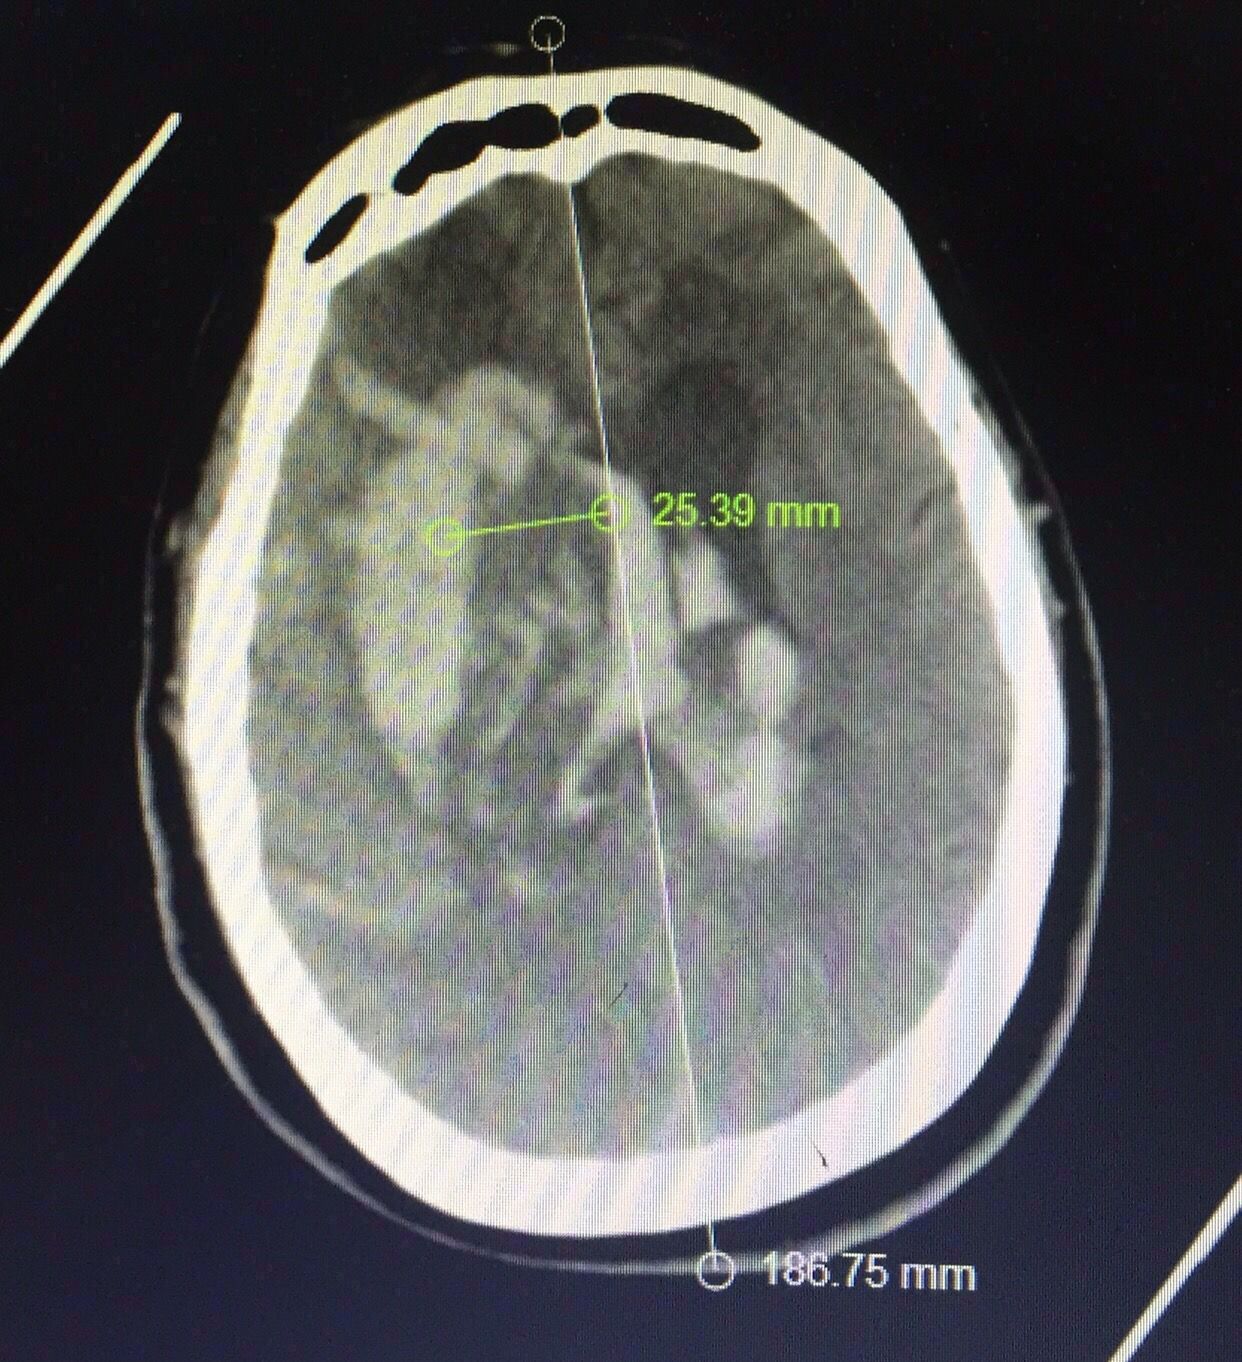

术后第7天复查,见上图,血肿引流比较充分。

认真阅片可知,血肿最大层面就是脑室额角层面,EVD的靶点就是额角室间孔位置,我们把血肿靶点也定在这一层,右侧血肿内,右侧额角室间孔位置偏右,如图↑↑

中线旁开2.5㎝平行矢状线穿刺右侧血肿;偏内穿左侧脑室

中线旁开2.5㎝可以让穿刺管几乎游走在所有的血肿层面内↓↓↓↓↓↓4张照片

Kocher点的验证↓↓↓

从最后复查的骨窗位可以看到钻孔的位置

定位还算准确

脑窗还可以看到穿刺管的路径↑

总结:对基底节血肿来说,穿刺的位置并不拘泥于颞部或前额部,冠状缝前的额中回区域也是不错的选择,当然要根据具体的血肿形态而定。